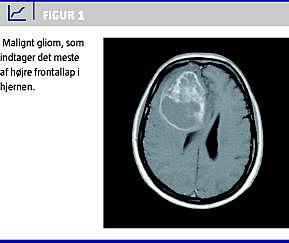

Gliomer er tumorer i hjernen og rygmarven, som udgår fra centralnervesystemets (CNS) støttevæv, glia. Ifølge WHO [1] klassificeres disse tumorer i fire grader, hvor grad 3 og 4 betegnes højgrads = maligne (Figur 1 ). Grad 4 kaldes også glioblastoma multiforme (GBM), grad 3 kaldes anaplastiske gliomer, som igen findes i undertyper bl.a. anaplastiske astrocytomer og anaplastiske oligodendrogliomer. Gliomerne er de hyppigste blandt de primære hjernetumorer (med ca. 5-600 pr. år i Danmark). De udgør hovedparten af de såkaldt neuroepiteliale tumorer, som udgør ca. 40% af alle primære hjernetumorer (som omfatter bl.a. meningeomer og hypofysetumorer) [2]. De maligne udgør ca. halvdelen til totrejedele af disse, og de er forbundet med en notorisk dårlig prognose. Den mediane overlevelse er omkring 14-15 måneder for GBM, noget længere for grad 3. Indtil for nylig var den gængse behandling af maligne gliomer kirurgi efterfulgt af fokal strålebehandling. Gliomer er ikke velafgrænsede, men vokser infiltrativt i hjernen, og når de er maligne, findes maligne celler i stor afstand fra selve tumoren, sågar i den modsatte hjernehemisfære [3]. Fokal behandling er derfor aldrig tilstrækkelig, hvorfor behandling med systemisk virkende medicin som kemoterapi er aktuel. Der er dog påvist en sammenhæng mellem radikalitet ved operation og prognose [4]. Man har i flere studier påvist en omend moderat effekt i størrelsesordenen af en median livsforlængelse på to måneder af systemisk kemoterapi i behandlingen af maligne gliomer [5, 6]. Standardbehandlingen i Danmark og flere andre lande er hos patienter med GBM det såkaldte Stuppregime, hvor kemoterapi (temozolomid) gives »konkomitant« (= samtidigt) med strålebehandlingen efterfulgt af seks serier adjuverende temozolomid [7, 8].